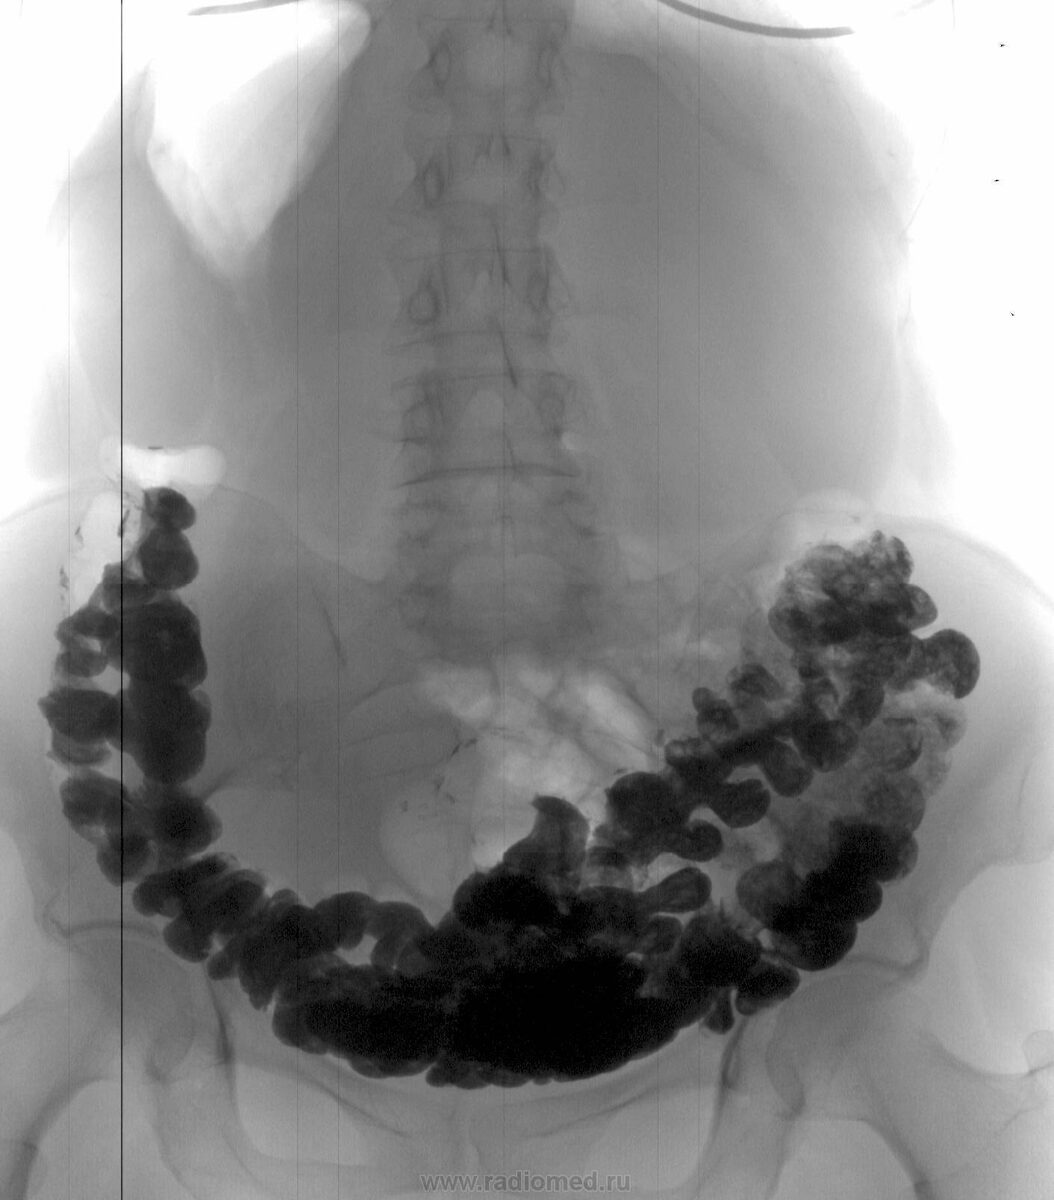

Ирригоскопия (рентген кишечника с контрастом). Камень виден как дефект наполнения.

Колоноскопия. Золотой стандарт. Врач видит камень воочию, оценивает его размер, положение и состояние слизистой. Может сразу же начать лечение.